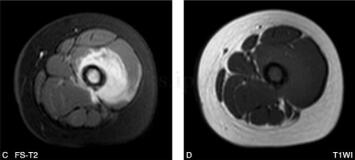

女,5岁,左下肢疼痛月余,近日加重,左下肢活动受限。病来无发热盗汗,无结核接触史。查体:左大腿肿胀,皮温略高,有压痛(图1、图2)。

图1 DR:左股骨上段略膨胀,局部骨皮质略增厚,其内可见小斑点状密度减低区,邻近软组织密度略增高

图2 MR:左股骨中上段髓腔内见长T1、长T2信号改变,局部肿胀增粗,左股骨局部外侧缘见层状骨膜反应,周围肌肉组织呈长T1、长T2信号改变